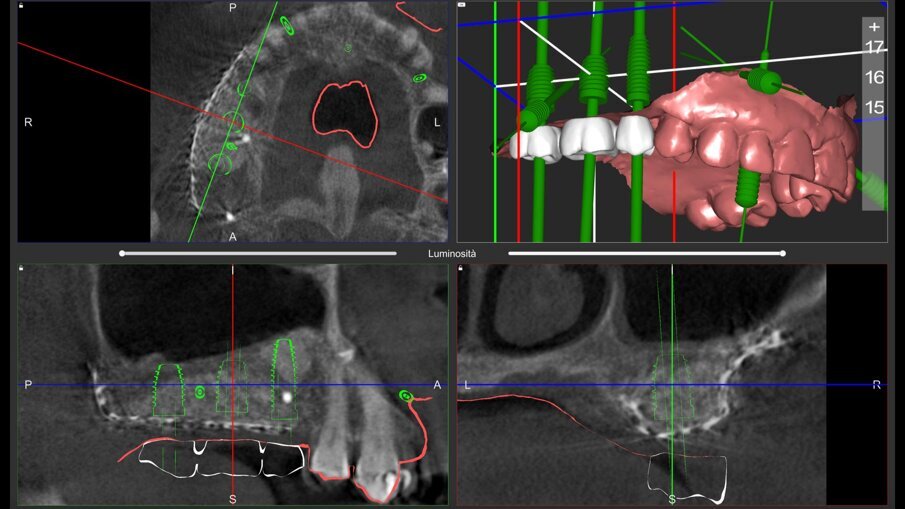

Il piano di trattamento è stato sviluppato utilizzando un flusso di lavoro completamente digitale. Pertanto, i files .DICOM ottenuti dalla CBCT pre-operatoria sono stati utilizzati per generare una ricostruzione 3D del mascellare, che ha permesso di eseguire la progettazione virtuale del volume osseo “ideale” per l’inserimento di 3 impianti in sede #15, #16, e #17. (Figg. 4, 5). Successivamente, è stata creata virtualmente la griglia customizzata corrispondente al volume aumentato nel mascellare della paziente (Fig. 6). Il giorno della chirurgia ricostruttiva (T0), è stata eseguita una profilassi antibiotica (2 g di amoxicillina con acido clavulanico e 500 mg di metronidazolo), una profilassi antinfiammatoria (20 mg di piroxicam), una sedazione cosciente x os (2 ml di delorazepam e 2 ml di diazepam), e disinfezione del cavo orale (risciacquo orale con povidone-iodio per un minuto, perossido di idrogeno per due minuti, e collutorio alla clorexidina 0,2% per tre minuti), e un’anestesia locale mediante articaina 4% contenente adrenalina 1:100.00018. L’esame obiettivo mostra la gravità del difetto osseo che determina un evidente difetto di volume sia in senso orizzontale che in senso verticale (Figg. 7, 8).

Dopo 9 mesi, è stata eseguita una seconda CBCT per valutare il volume di osso rigenerato e per pianificare la chirugia computer guidata (Fig. 23); i file .STL ottenuti dalla scansione 3D e i files .DICOM della CBCT sono stati utilizzati per pianificare l’inserimento degli impianti tramite una chirurgia computer guidata (Navimax, Biomax) (Fig. 24) . Il giorno della chirurgia implantare (T1), è stata eseguita un’incisione orizzontale para-crestale, per permettere l’esposizione della griglia e la sua rimozione, previa rimozione delle viti in titanio e dell’osso formatosi al di sopra di essa (Figg. 25, 26). L’esame clinico ha evidenziato una completa rigenerazione ossea del difetto osseo verticale, con assenza di pseudo-periostio o pseudo-periostio minore di 1 mm, di conseguenza pseudo-periostio di “classe 1” secondo la classificazione di Cucchi et al.20 (Figg. 27, 28). Successivamente, la dima chirurgica è stata posizionata e fissata nella posizione pianificata; i siti implantari sono stati preparati con frese progressive dedicate; e tre impianti conici (T3, Zimvie) sono stati inseriti nelle posizioni #15, #16 e #17, secondo la pianificazione protesicamente guidata eseguita precedentemente mediante il software da chirurgia guidata (Figg. 29-31). Gli impianti sono stati “sommersi”, attendendo la corretta osteointegrazione, ed è stata eseguita una chiusura per prima intenzione (Fig. 32). Dopo il posizionamento degli impianti, è stata eseguita una radiografia OPT (Fig. 33).